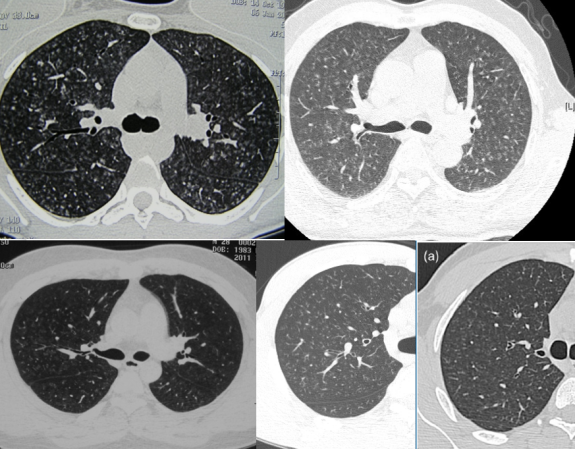

病例:男性,33岁,劳力性呼吸困难4年,加重3月,在治疗之前,我们看到的影像有些磨玻璃影、马赛克征,还有小叶中央型结节,并进行了外科肺活检。患者在从事铸造工作过程中间断接触异氰酸酯。停止工作暴露,并糖皮质激素经过治疗后,病情好转,但停用激素后又出现了肺部弥漫的磨玻璃影,肺功能也有所下降。

图:(从左至右)治疗前、脱离暴露+激素治疗10月、停激素18月

患者之后的检查过程中发现了光过敏、技工手、抗Jo-1抗体阳性,符合抗合成酶抗体综合征,所以这个患者的诊断是HP合并抗合成酶抗体综合征,经过治疗病情稳定。